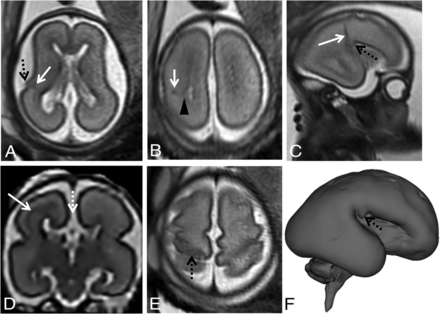

Example of associated partial CCA (white dashed arrow, D) in fetuses at 24 gestational weeks (A and B), 26 gestational weeks (C, D, F), and 31 gestational weeks (E). T2-weighted single-shot FSE images in the axial (A, B, E) and sagittal planes (C) and super-resolution 3D reconstruction of T2-weighted spin-echo FSE images through the coronal plane (D) and cortical surface (F). There is a malformation of cortical development with an abnormal “bump” in the insular region (dashed black arrow, A, C, F) and abnormal gyration in the posterior frontal cortex (dashed black arrow, E). There is a concurrent signal abnormality with low T2 signal intensity that follows the intermediate zone/subplate limit on the left (white arrow, A–D), also reaching the ventricular lining (black arrowhead, B), with slight ectasia of the homolateral posterior aspect of the lateral ventricle.